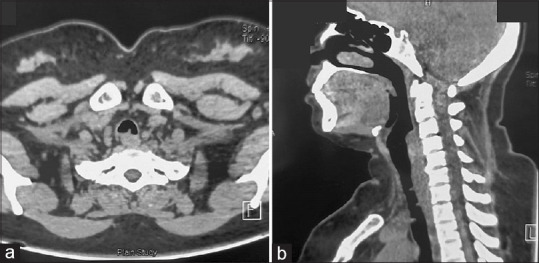

Multiple post-intubation tracheal granulomas presenting as stridor.

气管插管后多发气管肉芽肿,表现为喘鸣。